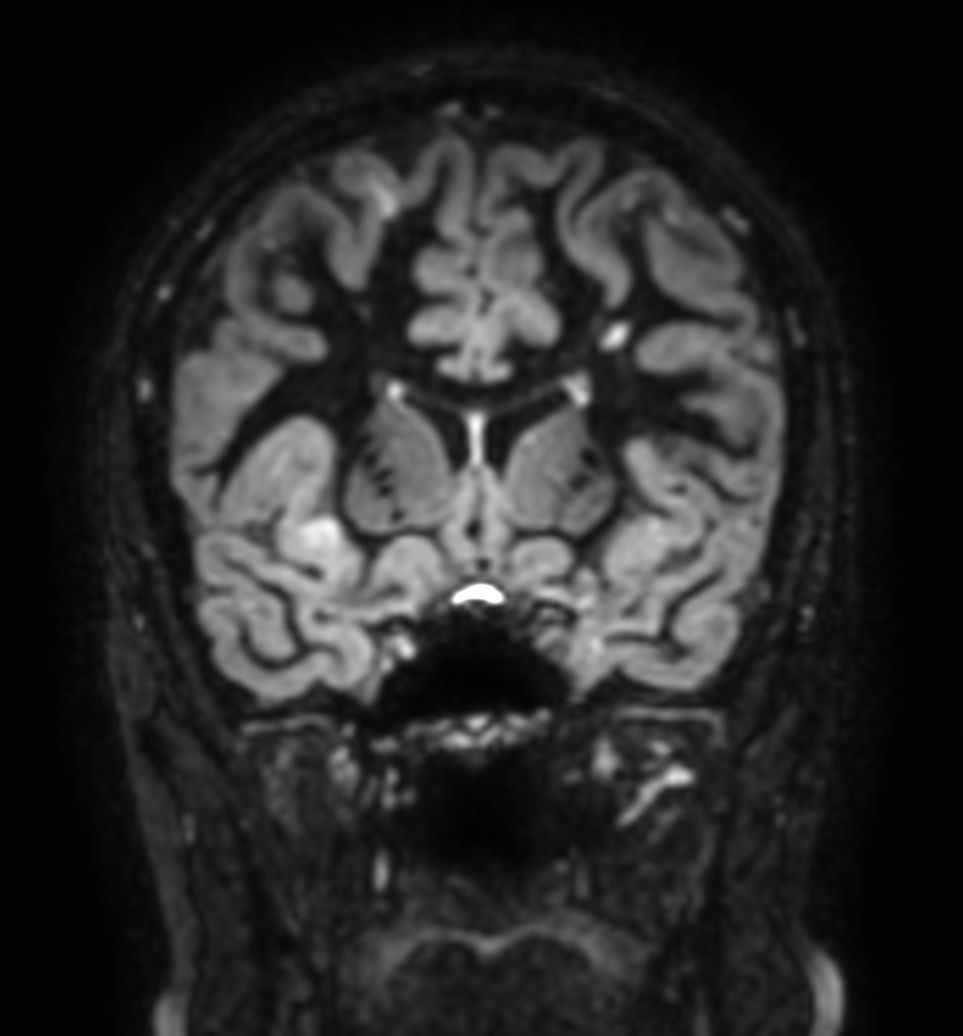

SWI sequence has a high sensitivity to enhance contrast for deoxygenated (venous) blood or calcium deposits. This may help, when used in combination with other clinical information, in the diagnosis of various neurological pathologies. 3D imaging lets you acquire high resolution data in multiple directions in one scan. Isotropic voxel size enables reformats in any plane without loss of resolution. FLAIR* requires offline post processing combining the contrast of 3D FLAIR and 3D SWI EPI into a single image. This enables the visualization of Central Vein Sign, mapping subcortical veins onto 3D FLAIR contrast images.